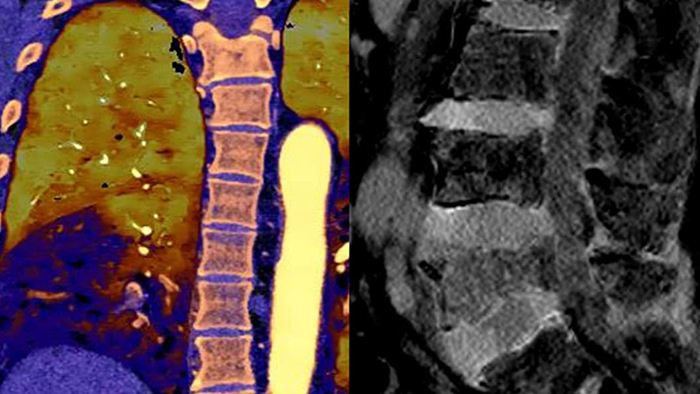

Conservez vos repères Une seule acquisition pour des données conventionnelles et spectrales rapides et à faible dose pour chaque patient, à chaque fois.

Toujours disponible 100% spectral, 100% du temps pour des résultats toujours disponibles même de façon rétrospective.

Notre scanner à détection spectrale Philips nous permet d'acquérir des données conventionnelles et spectrales en une seule acquisition, sans changement dans notre flux de travail actuel.